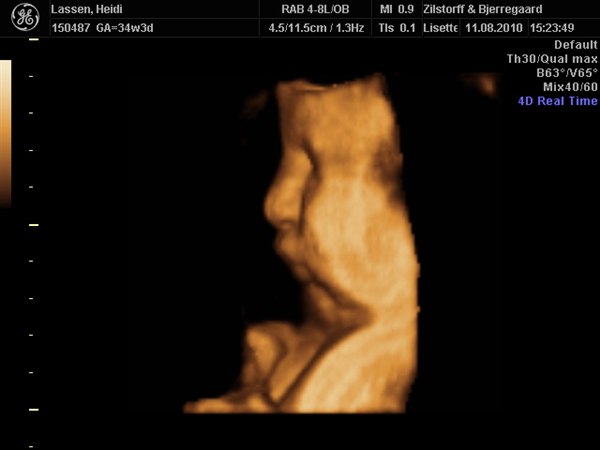

ja på det sidste billede af hende, ligner hun Emil når han blir utilfreds og sådan trækker trutmund/sur mine.

haha nåh ja det er rigtigt.. hun har en lidt sjov mund.. tror det er fordi hendes kinder er så store

vi kunne også se på 2d at hun har hår på hovedet